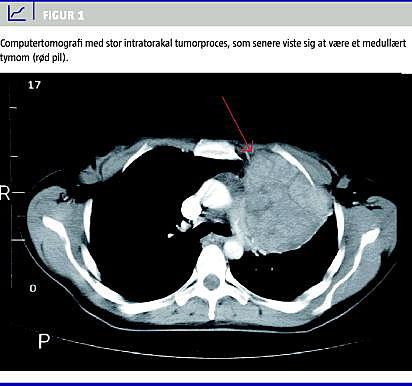

En 43-årig, tidligere rask kvinde blev grundet gentagne tilfælde af diaré udredt med koloskopi med biopsier, der viste uspecifik colitis uden holdepunkter for kronisk inflammatorisk tarmsygdom. Mesalazin havde nogen effekt på tilstanden. Pga. luftvejsinfek-tioner fik patienten seks måneder senere taget røntgen af thorax, hvor man uventet fandt breddeøget mediastinum. En computertomografi (CT) bekræftede en mediastinal tumor (Figur 1 ), som blev fjernet radikalt kirurgisk. Tumoren var et benignt medullært tymom.